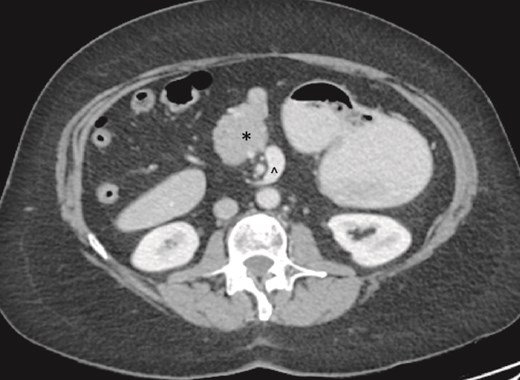

On examination, the abdomen was soft but mildly distended. Bowel sounds were heard, and the epigastrium was mildly tender. Standard bloodwork was normal. Review of an abdominal computerized tomography (CT) scan from 4 years prior showed congenital malrotation of the bowel, with the small bowel to the left of the midline and colon entirely to the right (Fig. 1). There was partial agenesis of the dorsal pancreas (Fig. 2), azygous continuation of the inferior vena cava (IVC), a retroaortic and retrocrural left renal vein, and an unremarkable spleen alongside some splenules. The PV traversed anterior to the first part of the duodenum (Fig. 3). There was relative narrowing of the distal stomach and the duodenum was nondilated.

Partial agenesis of the dorsal pancreas (*). Superior mesenteric vein (^) seen to the left of the superior mesenteric artery.